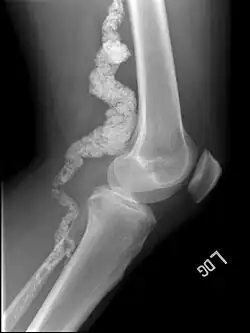

A knee x-ray of a person with ACDC

Arterial calcification due to deficiency of CD73 (ACDC) is a rare genetic disorder that causes calcium buildup in the arteries and joints of the hands and feet, and other areas below the waist.[1] Although patients exhibiting these symptoms have been identified as early as 1914, this disorder had not been studied extensively until recently. The identification of the specific ACDC gene and mutations occurred in 2011. ACDC is caused by a mutation in the NT5E gene, which prevents calcium-removing agents from functioning.[1][2] Patients with this mutation experience chronic pain, difficulty moving, and an increased risk of cardiovascular problems.[1][2] In experiments at the molecular level, treatment with adenosine or a phosphatase inhibitor reversed and prevented calcification, suggesting they could be used as possible treatment methods.[1] There is currently no cure for ACDC, and patients have limited treatment options, which focus primarily on the removal of blood calcium and improving mobility.[1][2]